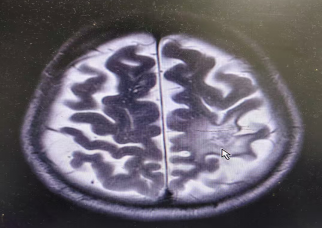

輔助檢查:2025/4/19 胸腹部CT:肺部及左腎上腺病灶穩(wěn)定(SD)。2025/4/19顱腦MR:左額葉原放療區(qū)域新見(jiàn)一不規(guī)則環(huán)形強(qiáng)化灶,伴明顯瘤周水腫,較2023年放療前基線影像顯著增大,符合腫瘤復(fù)發(fā)表現(xiàn)(圖1)。

1.顱腦MR可見(jiàn)轉(zhuǎn)移瘤及大面積水腫